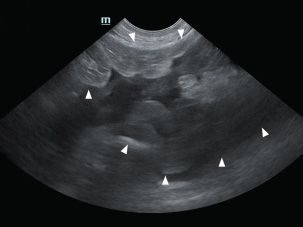

An 11-year-old intact male Siberian Husky was presented in acute hypovolemic shock. On physical examination, the patient was lethargic and exhibited tachycardia, tachypnea, and hypotension, with a recorded systolic/diastolic blood pressure of 58/31 mmHg. Abdominal radiographs were not diagnostic due to the loss of serosal detail secondary to intra-abdominal fluid accumulation. Hematologic evaluation revealed microcytic (mean cell volume, 58.4 fL; reference range, 61.6–73.5 fL) and normochromic (mean corpuscular hemoglobin concentration, 30 g/dl; reference range, 32–37.9 g/dl) anemia, with a packed cell volume (PCV) of 28.5% (reference range, 37.3%–61.7%). Additional abnormalities included hyperglycemia (231 mg/dl; reference range, 70–143 mg/dl), hyperamylasemia (4543 U/L; reference range, 500–1,500 U/L), hyperlipasemia (5,683 U/L; reference range, 200–1,800), and elevated D-dimer concentration (2 mg/dl; reference range, 0–0.3 mg/dl). Abdominal ultrasonography identified a well-circumscribed, round, lobulated mass measuring approximately 10 cm in diameter, located caudal to the stomach (Fig. 1). A large volume of peritoneal fluid was also present within the abdominal cavity (Fig. 2). Compared to the anechoic urine within the bladder, the peritoneal fluid appeared hyperechoic. Fluid collected via abdominocentesis showed a PCV of 28% (reference range, 37.3%–61.7%). Thoracic radiographs showed no evidence of pulmonary metastases or thoracic abnormalities.

Fig. 1. Abdominal ultrasonography showed a well-circumscribed, round, and lobulated mass approximately 10 cm large (white arrowhead), located caudal to the stomach.